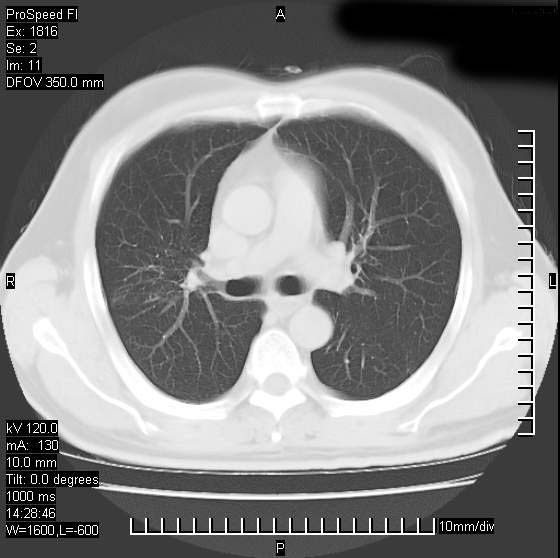

男性,50 ,肺结核9年,咳嗽,胸痛一周。右上肺见一厚壁空洞,周边有点样钙化,胸膜牵拉,洞壁较光整。诊断结核性空洞。有癌性的可能吗? 余肺野无异常,没有上传。

部分层面见空洞为近似新月形,洞壁内缘尚规整且近肺门侧,周围见索条影、卫星灶,结合病史,首先考虑肺tb可能大。

洞壁较厚内壁比较光整,两个病灶有关联性,纵隔淋巴结不大,考虑结核性空洞。

结核有可能,肺癌待排。空洞的前上还方见一软组织结节影。